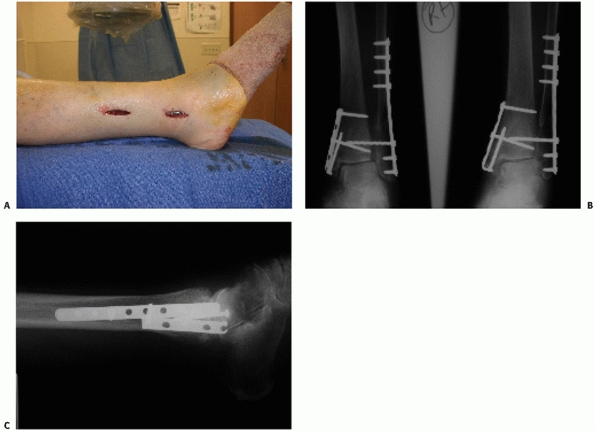

![]() |

FIGURE 57-5

During the gravity stress view, the patient is made to lie in the lateral decubitus position on the side of the affected ankle with the distal leg, ankle, and foot allowed to hang dependent off the end of the table while a mortise view is obtained. This patient positioning, in effect, acts to impart an external rotational force as in the manual stress view. |